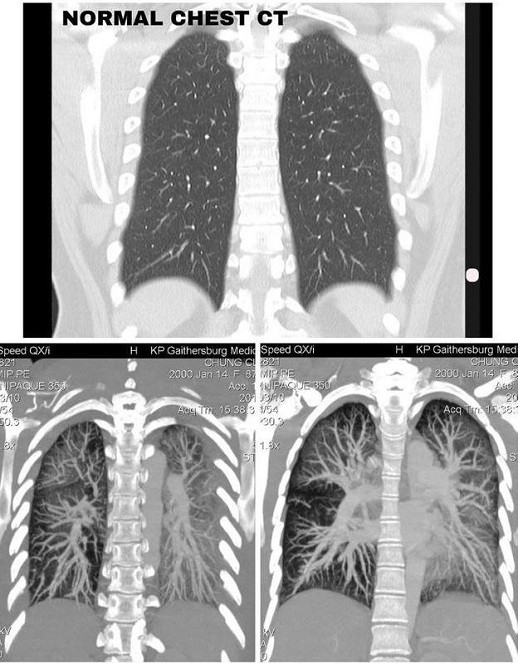

![]() |

| Lá phổi của một bệnh nhân 19 tuổi bị tổn thương nặng nề do hút thuốc lá điện tử, với các mô có màu trắng đục thay vì đen như bình thường. (Ảnh: Claire Chung) |

Bên cạnh đó, các thành phần trong thuốc lá điện tử còn gây nguy cơ khởi phát hen, gây COPD, viêm phế quản mạn, tim mạch, tâm thần kinh, suy giảm hệ miễn dịch, nghiện nicotin… Đáng lưu ý, việc hút thuốc lá điện tử thụ động cũng có tác hại tương tự thuốc lá thông thường.